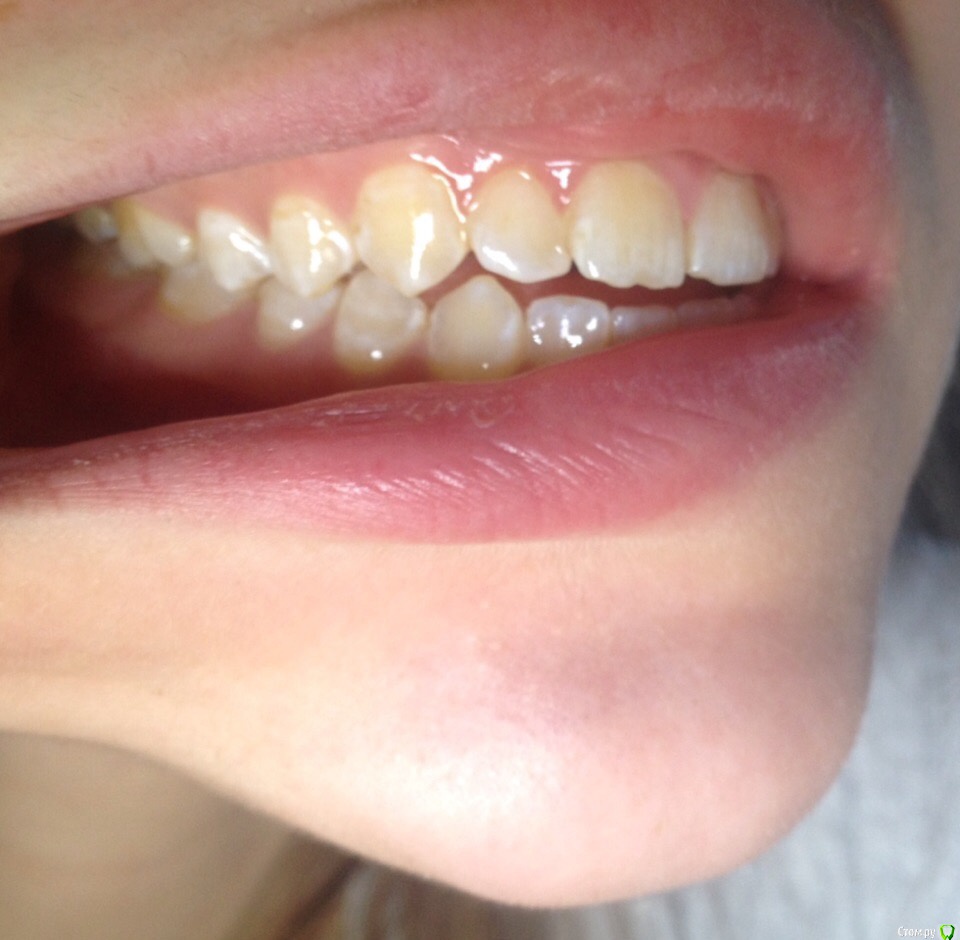

КошкинДом Опубликовано 3 сентября, 2019 Поделиться Опубликовано 3 сентября, 2019 Приветствую всех!Меня зовут Александра, мне 25 лет и я ипохондрик, переживаю в данный момент из-за своих зубов. Возможно кто-то из вас сможет дать мне совет Пол года назад у меня немного заболел левый ВНЧС, было неудобно спасть, затем все прошло и больше ничего не беспокоит до сих пор, только иногда хрустит в левом суставе и легкий дискомфорт в ухе после еды. Я заметила что в течении этих 6 месяцев мой прикус открылся ~2мм Вот мое фото 2017:А вот сейчас: Также прикрепляю два фото, ТРГ и ОПТГ: Мой вопрос: Меня сейчас ничего не беспокоит в моих зубах, можно ли и дальше спокойно жить? Если кто-то сталкивался с подобным дайте совет Всем хорошего дня 1 Ссылка на комментарий

krokomot Опубликовано 4 сентября, 2019 Поделиться Опубликовано 4 сентября, 2019 Открытый прикус требует лечения. Ссылка на комментарий